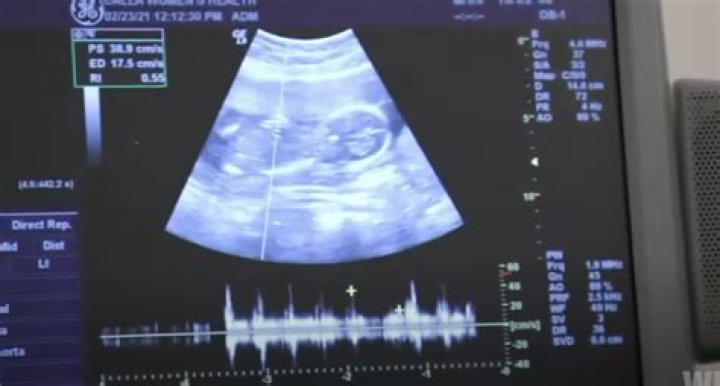

Audiences who tuned in to Episode 9 that aired on July 8 watched as JoJo and Tanice learned that they were expecting. The two made an appointment to see her doctor to make sure that everything was alright. The appointment went well, and the couple were ecstatic but not ready to tell anyone just yet. They were scared to let anyone know that Tanice was pregnant because they didn’t want to double back and explain if something went wrong during her pregnancy.